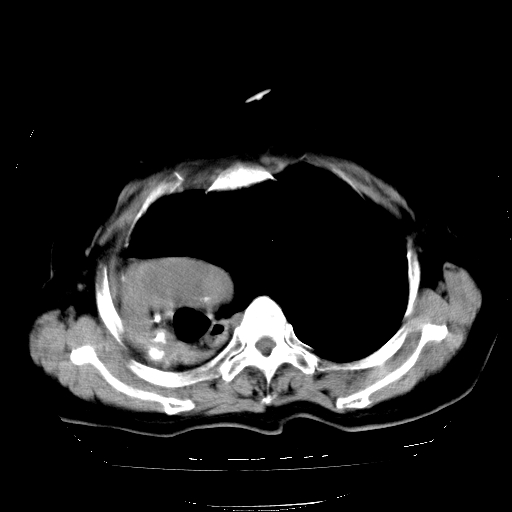

标题: CT23991:女,72岁,咳嗽、憋气一周。 [打印本页]

女,72岁,咳嗽、憋气一周,十年前曾患肺结核及胸膜结核。

1.右侧损毁肺伴胸膜钙化,2.左肺小结节灶,良性可能大,注意复查。3.肝脏左叶囊肿。4.先天性一侧肺不发育待出外(右侧胸廓无明显塌陷)。对比原片应该非常有帮助。